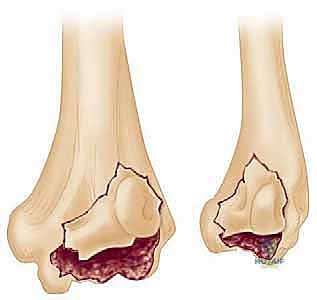

FIG 1 • Type 4 coronal shear fractures of the distal humerus.

- Bryan and Morrey (Modified by McKee):

- Type 1: Complete fractures of the capitellum. These typically involve a significant subchondral bone component.

- Type 2: Superficial subchondral fractures of the capitellar articular surface. These are often smaller, thinner articular fragments.

- Type 3: Comminuted fractures, displaying variable amounts of fragmentation.

- Type 4: Coronal shear fractures that include a portion of the trochlea as well as the capitellum as one piece. These are inherently more unstable and complex.